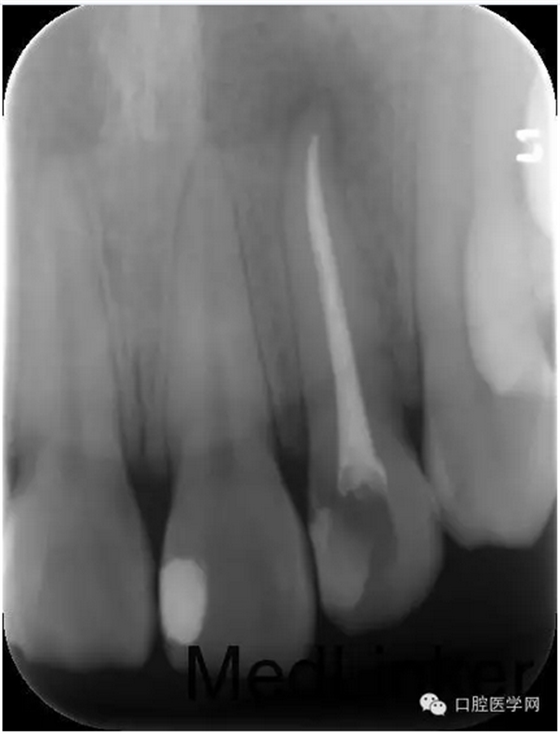

第四次:復(fù)診無(wú)不適。叩診無(wú)不適,無(wú)松動(dòng)。復(fù)查X線片,根尖密度減低區(qū)明顯減小,玻璃離子體部分去除,樹脂充填,調(diào)牙合,拋光。醫(yī)囑待18周歲后行冠永久修復(fù)。